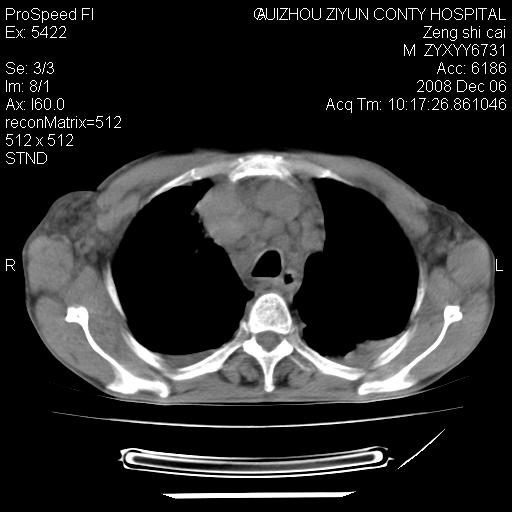

标题: CT16961:M、71岁,咳嗽半年,无血痰;胸片示右肺占位。 [打印本页]

标题: CT16961:M、71岁,咳嗽半年,无血痰;胸片示右肺占位。

右肺癌并纵隔淋巴结及胸膜转移可能性大

右肺癌并纵隔淋巴结及胸膜转移。建议气管镜

右肺纵隔型肺癌伴纵隔淋巴结及胸膜转移!

右肺纵隔型肺癌伴纵隔淋巴结转移!双侧胸水!

1)考虑右肺上叶纵隔型肺癌伴纵隔淋巴结转移。2)心包积液,双侧胸腔积液。

右肺癌并纵隔淋巴转移,腹膜后转移可能性大,两侧胸腔积液

右肺癌并纵隔淋巴结及胸膜心包转移,好多团团点点,看得有点想吐

右肺上叶纵隔型肺癌伴纵隔淋巴结转移。心包积液,双侧胸腔积液。

右上肺癌并纵隔淋巴结及胸膜转移。

建议强化!主要鉴别是淋巴瘤与肺癌淋巴结转移。

右肺纵隔型肺癌伴纵隔淋巴结及胸膜转移